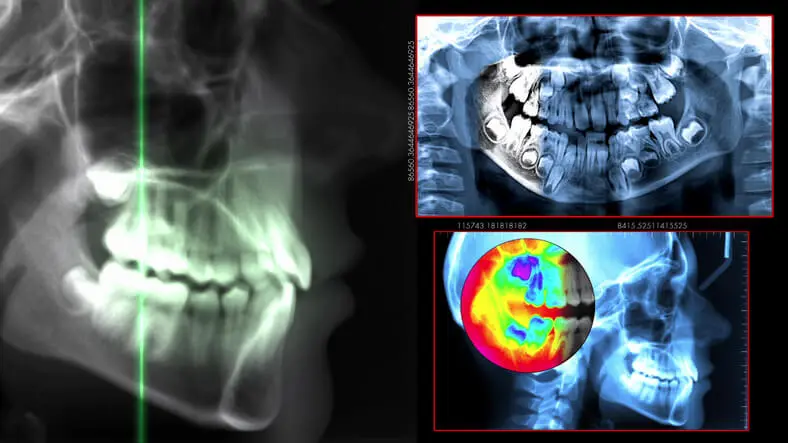

Radiographic Cephalometry 歯科 本 矯正 Radiographic Cephalometry 歯科 本 矯正 本の詳細情報

Radiographic Cephalometry 歯科 本 矯正 本。Radiographic Cephalometry 歯科 本 矯正 Radiographic。cephalometry-ceph-tooth-dental。「Radiographic Cephalometry」DVD付き書き込みはありません。【裁断済】 即戦力が身につく胸部の画像診断。中古品、自宅保管にご理解お願いいたします。Image of lateral cephalometric radiograph. | Download。DVDは未開封です。写真にて状態をご確認ください。toy 胸部。大天使ガブリエルオラクルカード。#歯科#矯正#セファロ